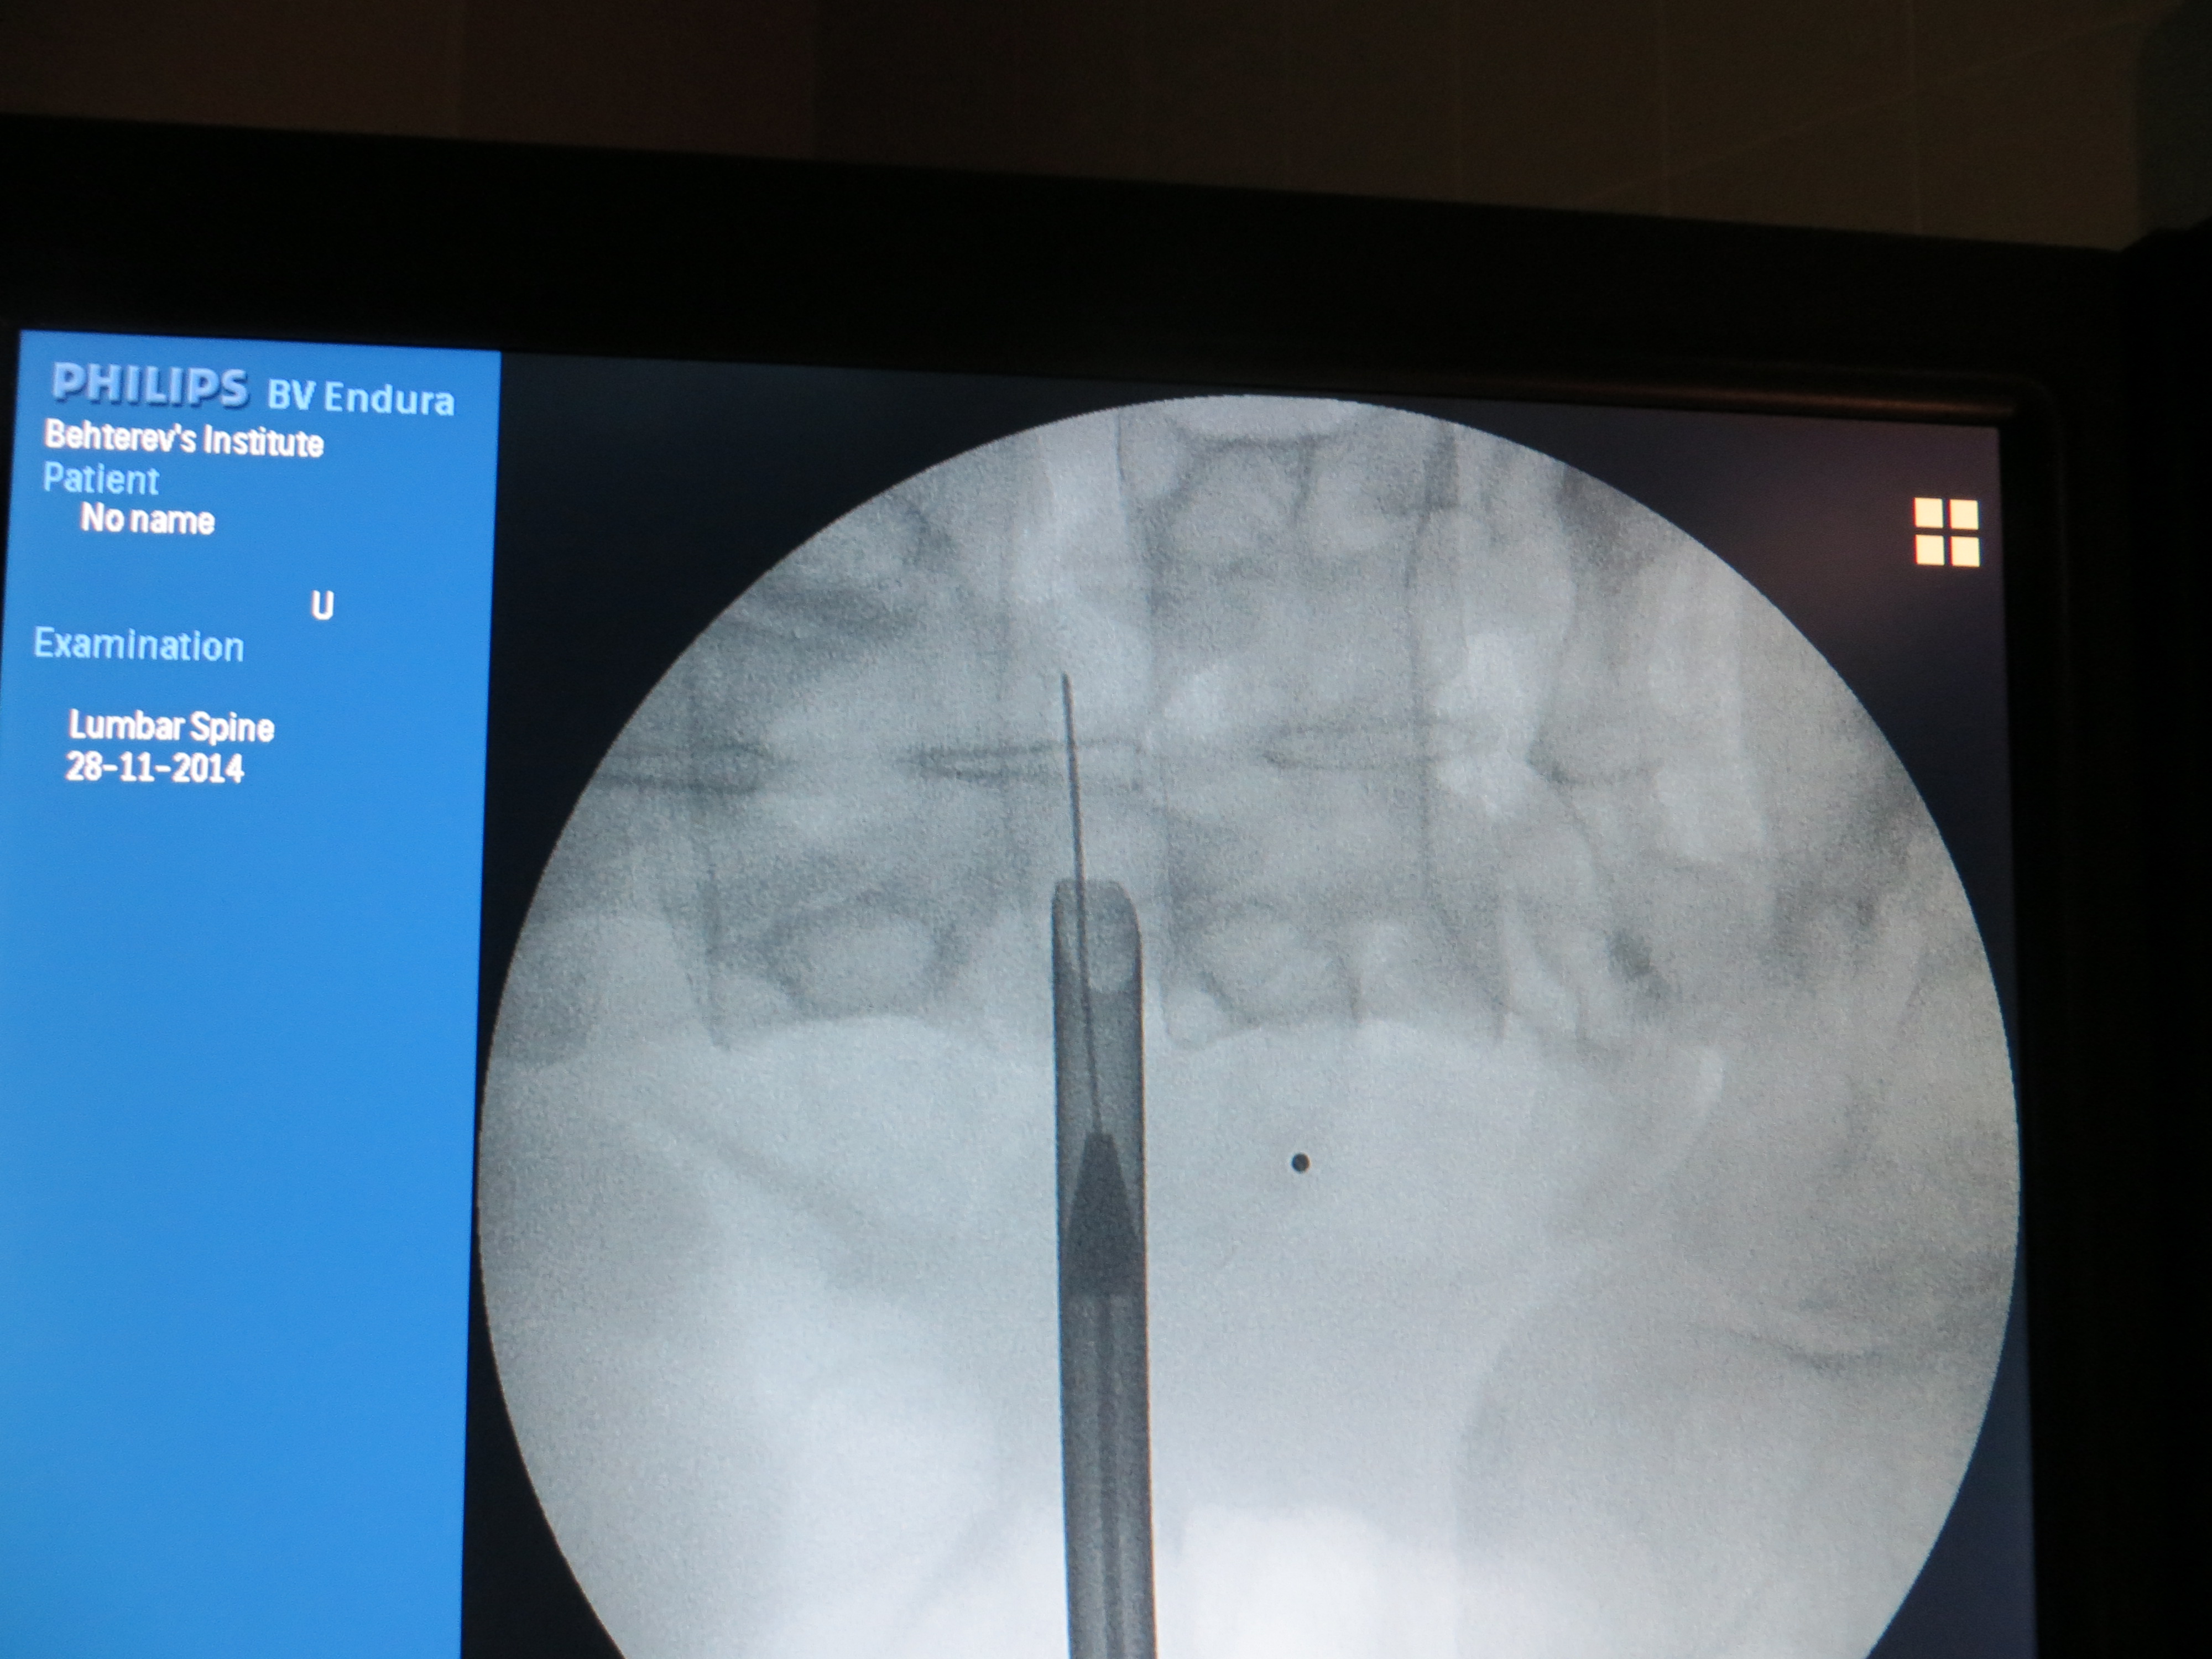

В Институте имени Бехтерева хирургическое лечение позвоночника проводится с целью предотвращения сдавления спинного мозга и развития осложнений при остеохондрозе и межпозвоночных грыжах. К сожалению, деструктивные изменения в суставах позвонков встречаются сегодня даже у пациентов молодого возраста. Но в нашем институте созданы все условия для диагностики и лечения заболеваний позвоночного столба.

Современное оборудование позволяет выявлять межпозвоночные грыжи любой локализации и размера. Опытные невропатологи и нейрохирурги мастерски владеют техникой работы на инновационных аппаратах, а малоинвазивные оперативные вмешательства позволяют избежать развития инфекционных осложнений и значительно сократить время реабилитационного периода. После операций на позвоночнике крайне важно организовать эффективные восстановительные мероприятия. Для этого наши специалисты составляют индивидуальные программы реабилитации, активно применяя ЛФК, тренажеры и физиопроцедуры. В комплексе подобный подход дает отличные результаты.

В Институте имени Бехтерева проводятся как традиционные хирургические вмешательства, так и эндоскопические операции. Возможности малоинвазивных методик позволяют под визуальным контролем эндоскопа и с минимальной травматичностью тканей удалять межпозвоночные грыжи. Такие операции не приводят к обильной кровопотере и хорошо переносятся даже пациентами с хроническими заболеваниями. Во время операции (дискэктомии) хирурги удаляет межпозвоночную грыжу вместе с поврежденными структурами диска, при этом риски развития осложнений минимальны. После вмешательства пациенты быстро восстанавливаются, не испытывая никаких двигательных ограничений в дальнейшем.

Оперативное лечение, в зависимости от медицинских показаний, может быть как «малоинвазивным» - это микродекомпрессия (т.е. устранение сдавления спинномозговых корешков, дискэктомия) с использованием различных микрохирургических техник, так и «открытым» - интерламинарное транслигаментарное удаление грыжи диска.